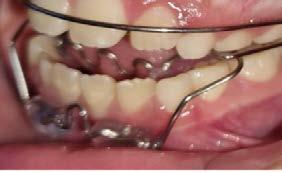

Se observó en la evaluación asimetría facial, tercio inferior aumentado, en la regla de quintos las líneas interpupilares no coinciden con la comisura labial, muestra 2/3 de las coronas superiores al sonreír y perfil retrusivo ocasionado por la distoclusión mandibular (Figura 1).

Su fonación no es clara, ya que presenta congestión nasal y hábito de lengua. Las fotografías intraorales de inicio se muestran en la Figura 2

Figura 2. Fotografias intraorales: A) fotografía de en oclusión, mordida abierta, línea media desviada. B) fotografía lateral, clase II subdivisión I.